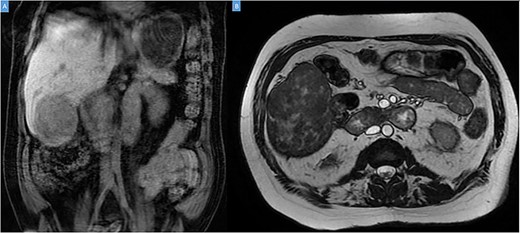

A 49-year-old male presented with a large right hepatic lobe mass on abdominal computed tomography (CT) scan ordered for non-specific abdominal pain. He had a past medical history of type 2 diabetes mellitus, glaucoma and deafness due to mumps. The physical examination was normal, with a body mass index of 22 kg/m2 and no previous abdominal surgeries. CT scan (Fig. 1A and B) and magnetic resonance imaging (MRI; Fig. 2A and B) revealed a 10.7 × 7.6 × 8.9-cm mass involving the liver’s segments V–VI with heterogeneous enhancement and areas of calcification.

(A, B) Coronal computed tomography of the abdomen showing a large tumor on liver’s segments V–VI with heterogenous contrast enhancement.

Coronal (A) and axial (B) sections of MRI showing the peripheral liver tumor.